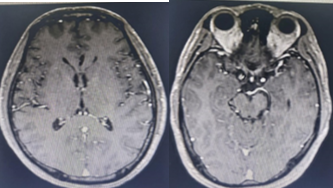

Chụp Cộng hưởng từ sọ não (4/4/2019):

Hình 1:  Hình ảnh chụp MRI sọ não: Nhiều nốt ngấm thuốc mạnh rải rác ở nhu mô não trên và dưới lều, theo dõi tổn thương thứ phát (mũi tên đỏ).